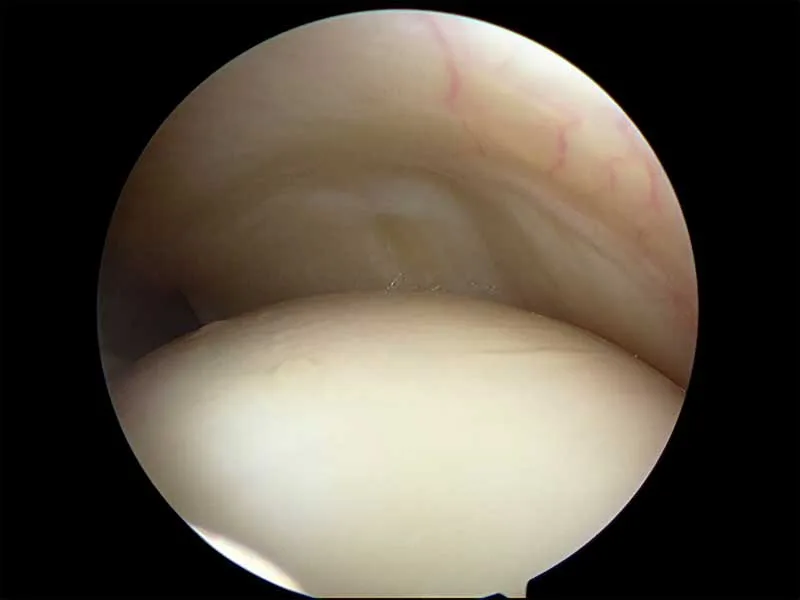

Below are key-hole surgery images inside two different shoulders looking at the smooth cartilage of the humerus (arm bone) below and the rotator cuff tendon above.